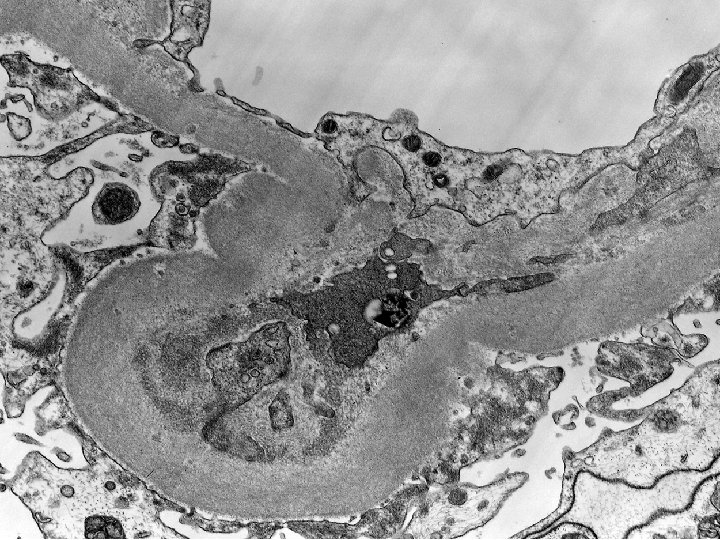

Diagnosis Renal Biopsy (7 yrs post-transplantation): -Diffuse glomerulosclerosis with features suggesting recurrent or de

Diagnosis Renal Biopsy (7 yrs post-transplantation): -Diffuse glomerulosclerosis with features suggesting recurrent or de novo diabetic nephropathy. -Moderate parenchymal atrophy and scarring. -Slight numbers of paramesangial deposits suggesting superimposed mild IC GN. Banff scores: g 0 cg 1 i 1 ci 2 t 0 ct 2 v 0 cv 2 ah 2 mm 2